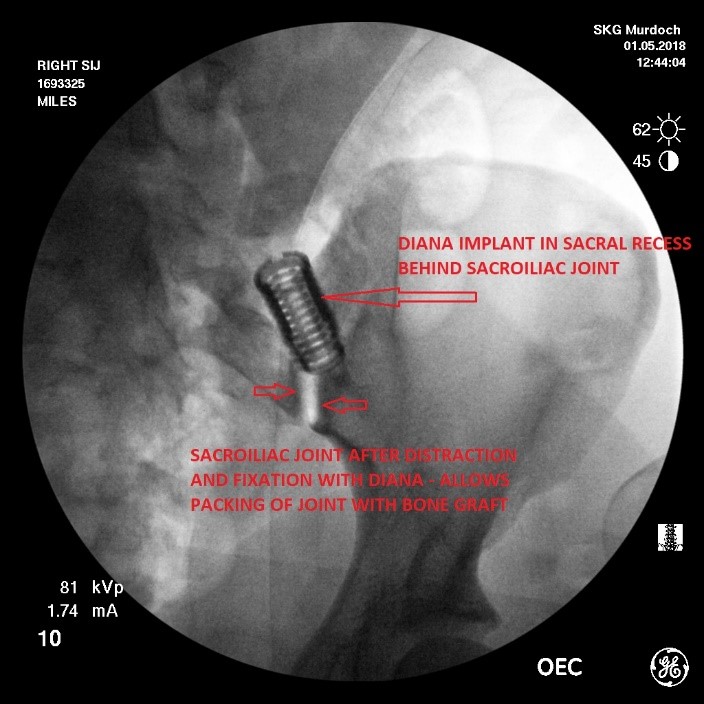

2 & 3. Distraction and fixation of the sacroiliac joint –the sacroiliac joint is indirectly distracted by distracting the medial (sacral) and lateral (iliac) boundaries of the sacral recess. To achieve this a guide pin is implanted using fluoroscopic control into the iliac bone of the pelvis. Positioning and trajectory of the guide pin is an essential component of the procedure and requires careful interpretation of fluoroscopic images performed in the antero-posterior (forward-backward), lateral and oblique planes.

Once the guide pin is positioned correctly and confirmed on the 3 fluoroscopic views, the sacral recess is progressively distracted using a series of progressively larger helical instruments until an appropriate degree of distraction of both the sacral recess and indirectly the underlying sacroiliac joint is achieved.

Once a satisfactory degree of distraction of the sacroiliac joint has been achieved, fixation of the distraction must then be obtained. This is achieved by implanting a DIANA screw sized to match the distraction obtained with the helical instruments.

4. Sacroiliac joint fusion – once the sacroiliac joint has been distracted and fixation of the distraction has been obtained by positioning of the DIANA screw, the exposed sacral recess and sacroiliac joint is then packed with bone graft. This component of the procedure is the most essential element of the whole surgery. The progressive development of a solid consolidated fusion mass within the sacral recess over the 6-9 month period after the surgical procedure maintains the distraction/fixation of the sacroiliac joint achieved with implantation of the DIANA screw and painful of the degenerative sacroiliac joint.